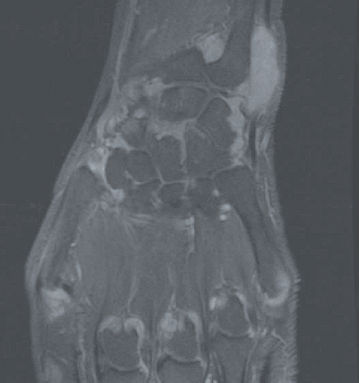

La polyarthrite rhumatoïde (PR) est une maladie auto-immune mais dans laquelle les auto-anticorps que sont le facteur rhumatoïde (FR) et les anticorps anti-peptides citrullinés (ACPA ; également appelés anti-CCP) ne sont pas constants : les PR appelées « séropositives » (FR+ et/ou ACPA+, qu’il conviendrait mieux de dénommer immuno-positives) représentent 75 à 80% des PR. Il reste donc 20 à 25% des PR séronégatives (FR- et ACPA-) dont la reconnaissance précoce est rendue plus difficile par l’utilisation des critères de classification européens-américains ACR/EULAR 2010 où le poids des auto-anticorps est très important (Tableau 1). La question de savoir s’il existe une seule PR avec deux visages ou deux maladies de physiopathologie différente reste débattue. Dans le diagnostic (et le suivi) de ces formes séronégatives, comme dans les formes séropositives, l’intérêt de l’échographie articulaire a été récemment souligné. L’IRM a également un intérêt pour la mise en évidence des synovites mais est ciblée sur une articulation ou un groupe articulaire alors que l’échographie permet une analyse de très nombreuses articulations (Figure 1). Un autre axe d’intérêt est représenté par les formes très précoces de PR, avec cliniquement de simples arthralgies mais associées à des auto-anticorps (FR/ACPA), situation où des essais d’intervention thérapeutique ont été menés récemment où sont en cours.

Figure 1. Exemple d’IRM du poignet et des métacarpo-phalangienne au cours de la PR en poussée